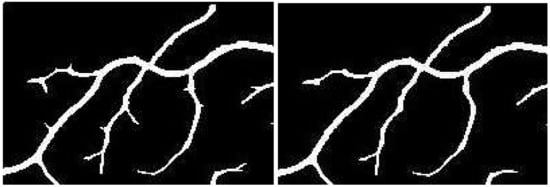

Figure 6. Segmentation results of: (a) Basic line detector; (b) Poor response at major vessels and vessel crossings; (c) Proposed method; (d) Improved response at critical points. This shadow removal happens largely due to alignment of line filter orientation with that of directional image it is operating on.